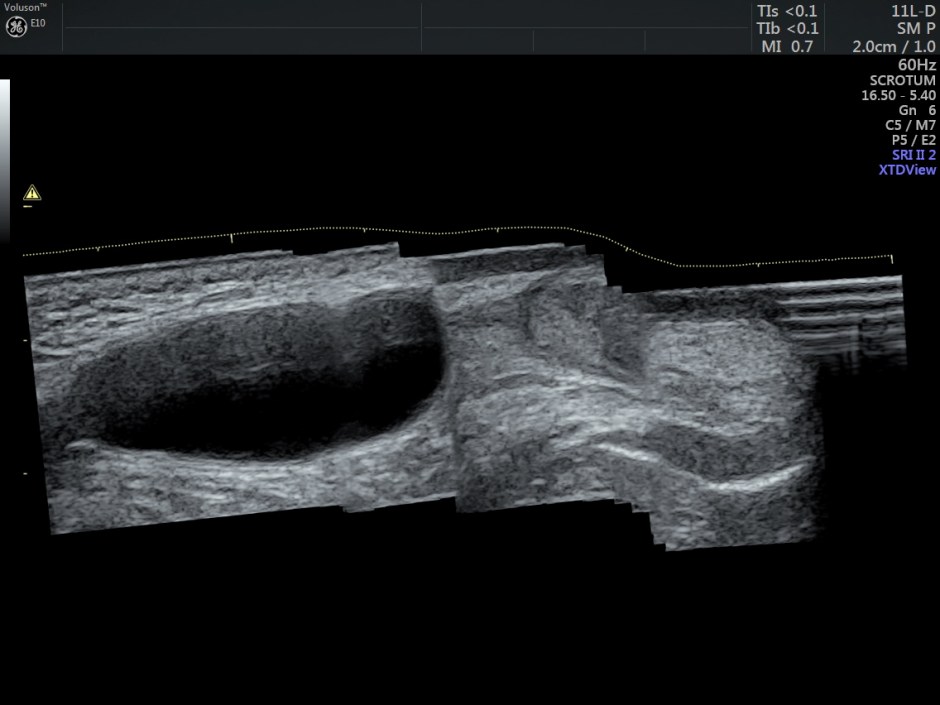

Panaoramic view of the same is given below.

It is a loculated fluid collection along the spermatic cord, separate from the testis and the epididymis and located above them.

An encysted hydrocele is enclosed between two constrictions at the deep inguinal ring, just above the testis. It does not communicate with the peritoneum.

An encysted hydrocele may be located anywhere along the spermatic cord. It may be any size or shape, but it does not change with increased peritoneal pressure. At US, an ovoid or round mass is seen in the groin along the spermatic cord; internal echogenicity varies depending on the contents. The presence of cholesterol deposits may explain an isoechoic appearance of the mass.

This appears to be a ENCYSTED HYDROCELE OF THE SPERMATIC CORD.